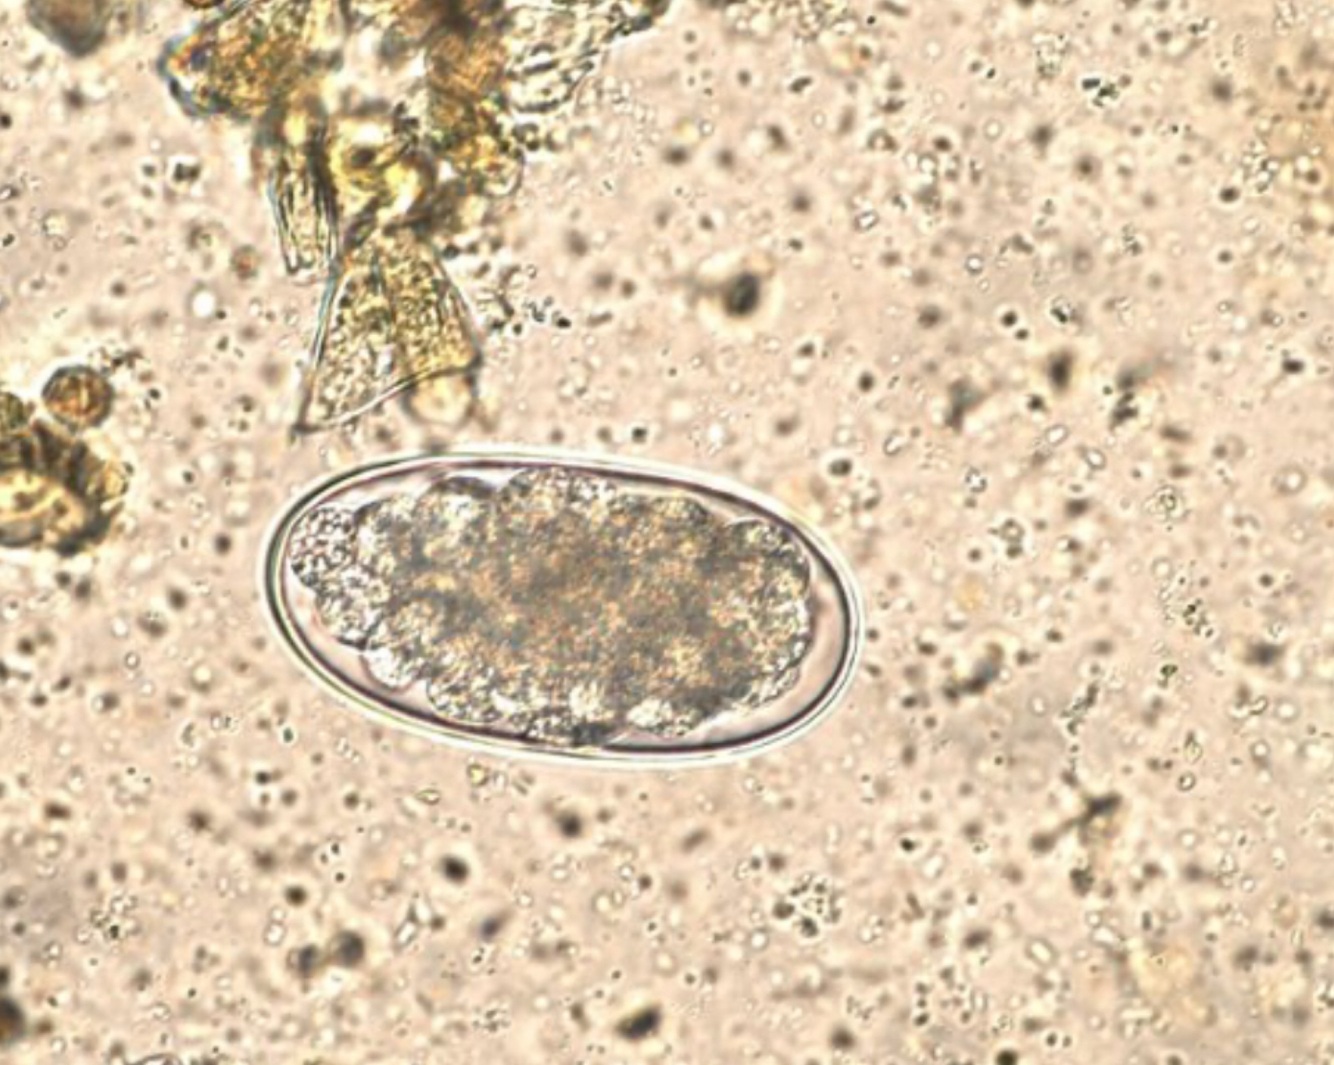

A 4-year old male Thoroughbred horse presents to you for colic. During your work up, you note a painful enlargement at the root of the mesentery on rectal palpation. You suspect that the cause of the horse’s colic are adults from the egg shown in the picture below. Which of the following drugs effectively kills the adult organisms that can cause this condition?

Colic with an associated painful mass at the root of the mesenery is suspicious for verminous arteritis caused by damage to the cranial mesenteric artery and its branches by Strongylus vulgaris. The strongyle egg shown in the picture confirms the cause in this question.

A number of anthelmintics are effective including benzimidazoles, pyrantel and ivermectin.

Praziquantel is effective against tapeworms. Rifampin and metronidazole are antibacterial drugs.